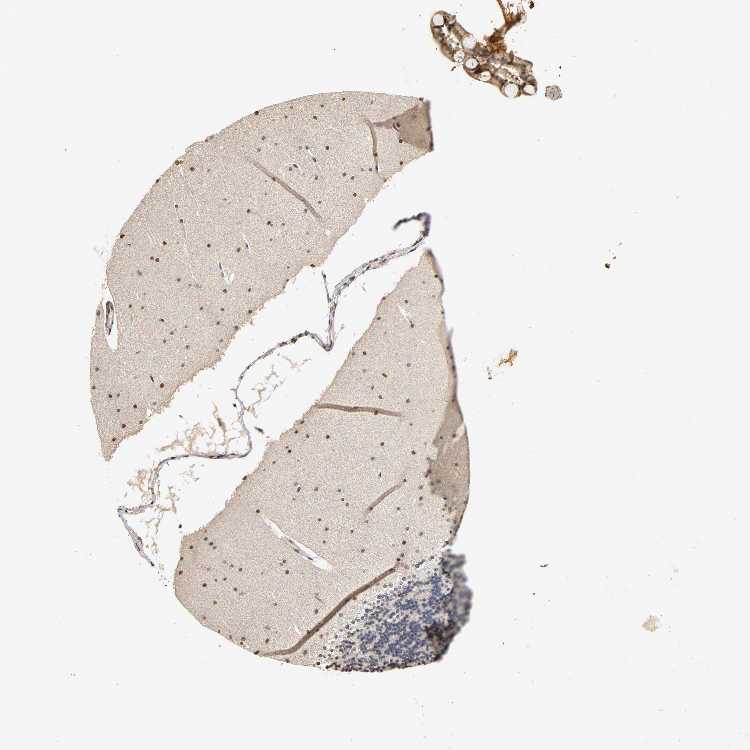

CEREBELLUM - Antibody stainingi

Antibody staining in the annotated cell types in the current human tissue is reported as not detected, low, medium, or high, based on conventional immunohistochemistry profiling in selected tissues. This score is based on the combination of the staining intensity and fraction of stained cells.

Each image is clickable and will lead to virtual microscopy that enables deeper exploration of all samples and also displays staining intensity scores, fraction scores and subcellular localization as well as patient and tissue information for each sample.

Antibody HPA038057Antibody CAB005375

Purkinje cells MediumNot detected

Cells in granular layer Not detectedNot detected

Cells in molecular layer Not detectedHigh